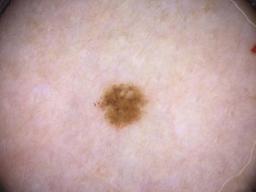

ISIC_8336318

Clinical

| Field | Value |

|---|---|

| age_approx | 40 |

| anatom_site_1 | Trunk |

| anatom_site_2 | Anterior trunk |

| anatom_site_3 | Anterior abdomen |

| clin_size_long_diam_mm | 6.19 |

| diagnosis_1 | Malignant |

| diagnosis_2 | Malignant melanocytic proliferations (Melanoma) |

| diagnosis_3 | Melanoma Invasive |

| diagnosis_4 | Melanoma Invasive, Superficial spreading |

| diagnosis_confirm_type | histopathology |

| image_manipulation | instrument only |

| image_type | TBP tile: close-up |

| lesion_id | IL_5097969 |

| mel_thick_mm | 0.40 |

| patient_id | IP_8989787 |

| sex | male |

| tbp_tile_type | 3D: white |